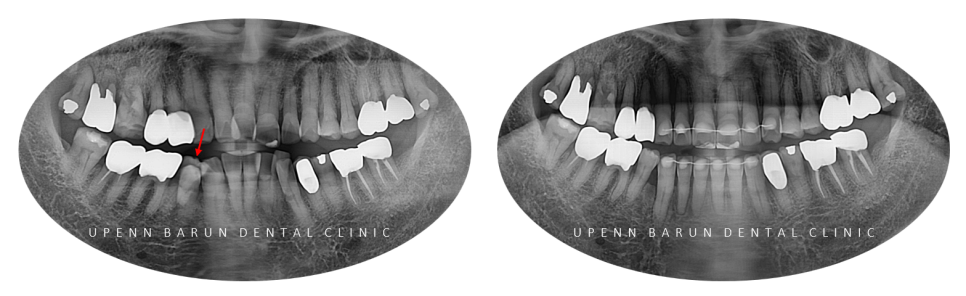

교정 전 안쪽으로 뻗쳐 있는 치아, 교정 후

환자분께서는

오른쪽 아래 음식물이 자주 껴서 불편하고

앞니가 삐뚤빼뚤해 오래도록 신경이 많이 쓰이셨다고 합니다.

윗니는 비발치로,

아랫니는 공간 확보를 위해

우측 아래 옆으로 많이 튀어나온

1개 치아의 발치가 필요한 상황 이었답니다.

1st ClinCheck(32개)

교정기간 23/3~24/1

첫번째 클린체크에서 32개의 장치로 인비절라인을 진행해드렸는데요